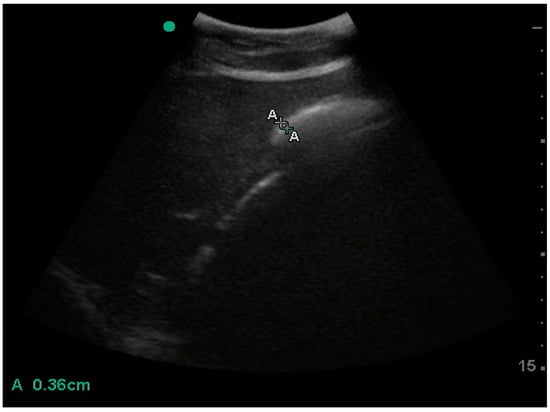

| Oesophagus | wall thickness | 3.6 (0.7) | 3.5–4.1 | 2.7 | 3.0 | 4.1 | 4.3 | 2.3 | 4.9 | 2.6 |

| diameter | 18.9 (4.8) | 18.5–23.3 | 11.4 | 14.4 | 22.3 | 23.5 | 10.1 | 24.6 | 14.5 | |